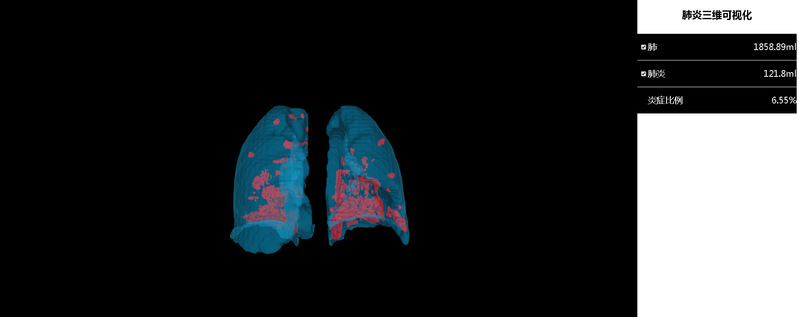

经过多轮论证和科学对比分析,该系统能够较好地实现多期新冠肺炎患者肺部器官和病灶的快速识别,并实现三维可视化,时间效率较目前主流软件大大提高,有效提升了医生诊断的工作效率,同时可以计算出肺炎体积并进行定量分析,作为诊断的重要参考依据。

肺部与肺炎组织三维重建结果